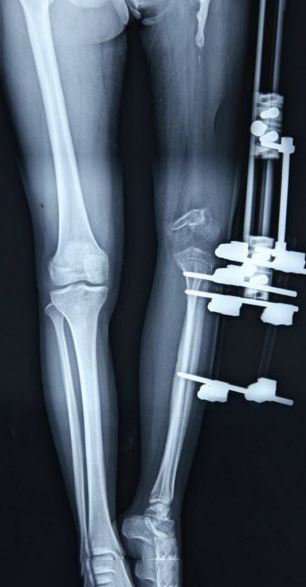

Բժշկի խոսքով՝ բուժման ծրագիրը բաղկացած է եղել երկու փուլից:

Առաջին փուլը եղել է ձախ ոտքի երկարացումը, իսկ երկրորդ փուլում վիրահատություն է արվել, որի ժամանակ փոխարինվել են ձախ ծնկի եւ կոնքազդրային հոդերը:

2012-ի հոկտեմբերից 2013-ի հոկտեմբերը Սյույը ենթարկվել է 4 վիրահատության: Նրա ոտքը երկարացնելու համար ստորին ձախ վերջույթի մեջ լայնացուցիչ է տեղադրվել:

Սյույն ամեն օր շրջել է պտուտակը, որպեսզի քիչ-քիչ ձգի ոսկորը:

Ոտքը երկարացնելու համար Սյույին մեկ տարի է անհրաժեշտ եղել: Դրանից հետո նրան հոդերի փոխարինման վիրահատություն է արվել: Աղջկա բուժումն ավարտվել է այս տարվա փետրվարի վերջին, և բժիշկների խոսքով՝ մի քանի ամիս վերականգնվելուց հետո նա կկարողանա նորմալ քայլել: